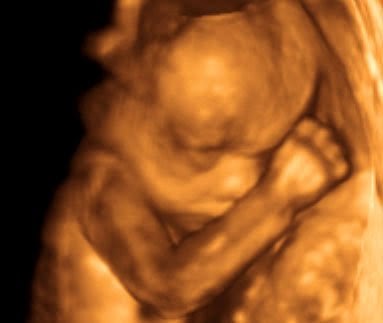

Ayrintili Ultrason Goruntusu 21 Haftalik 21 Week Youtube